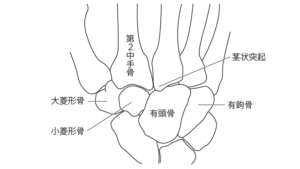

僧帽筋切除術では、外科医は僧帽筋と呼ばれる手首の付け根の骨を切除します。台形は小さな骨で、最大直径が 1 インチ未満です。 CMC 関節形成術では、除去された骨が人工インプラントに置き換えられます。

- その後、外科医は僧形骨を除去し、インプラントと置き換えます。

- 癒合(関節固定術):プレートまたはネジを使用して、僧形骨を親指の付け根の長く細い骨に癒合します。

- 僧帽筋切除術:僧帽筋の骨を外科的に除去します。